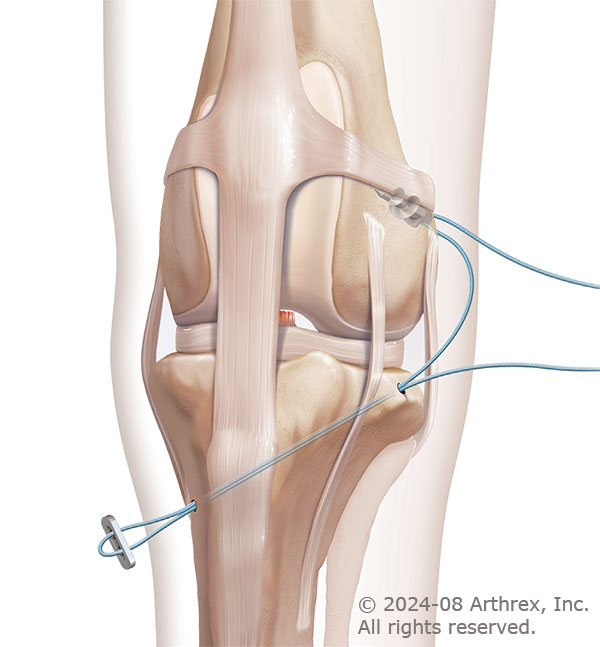

The Anchor Lock surgery utilizes an implanted anchor in the femur bone to securely fixate a suture at points biomechanically similar to the CCL. This prosthetic material has been used with success in human joint stabilizing procedures and provides the temporary stabilization necessary for scar tissue to form and provide long term joint stability.

During the Anchor Lock surgery an anchor implant is placed on the back of the femur bone to fixate a special suture. A tunnel is drilled through the tibia bone and the suture is run through the tunnel and around a surgical button.

The suture is tightened to pull the bones into alignment and tied to hold the knee in place.

Photos courtesy of Arthrex Vet Systems. © 2024-08 Arthrex, Inc. All rights reserved.